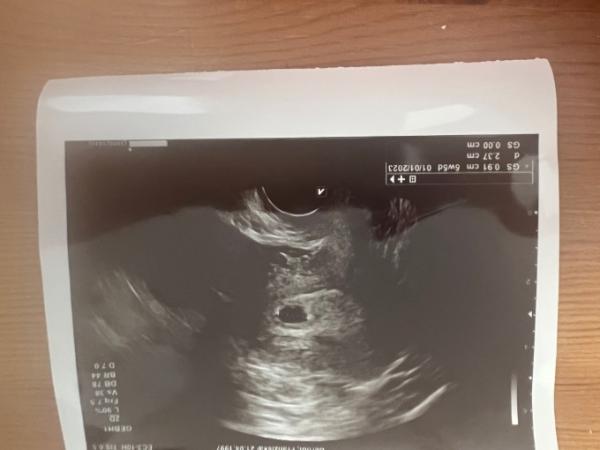

Ist da wohl ein Embryo zu sehen

Bild zu Ist da wohl ein Embryo zu sehen - Forum für Januar - Mamis

Also ich sehe nur eine Fruchthöhle. Was sagt denn dein Arzt dazu? VG Lucky_me

Auf jeden Fall eine Fruchthöle wie weit bist du den beim nächsten us sieht man dann bestimmt ein Baby herzlichen Glückwunsch